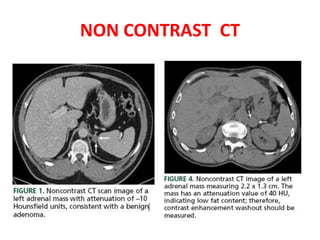

NON CONTRAST CT

CONTRAST ENHANCED CT

The enhancement washout = (43 - 22)

: (43 - 9) = 62% indicating a fast

washout characteristic of an adenoma.

The enhancement washout= (43 - 22) : (43 - 9) = 62% indicating a fast washout characteristic of an adenoma.